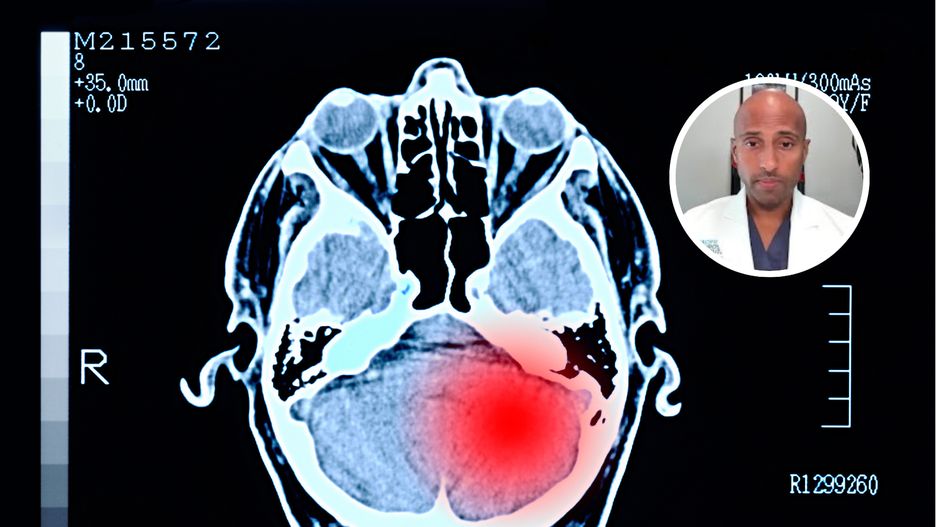

Typowy objaw guza mózgu. Neurochirurg: Nigdy nie powinien być ignorowany

Co roku na świecie diagnozę nowotworu mózgu słyszy około 322 tys. osób. W Polsce choroba dotyka rocznie nawet ok. 2375 pacjentów. Jeden z objawów choroby łatwo zignorować, choć jest charakterystyczny dla guza.

mNietypowy ból głowy może świadczyć o guzie mózgu

- Najczęściej spotykane guzy mózgu należą do dwóch szerokich kategorii: guzy pierwotne, powstające w tkance mózgowej, oraz guzy przerzutowe, będące następstwem przerzutów nowotworów zlokalizowanych poza mózgiem - wyjaśnia neurochirurg dr Walavan Sivakumar. Dodaje, że guzy przerzutowe (przerzuty do mózgu) zdarzają się częściej niż pierwotne – według niego nawet o ok. 50 proc.

Charakterystyczny objaw

Eksperci podkreślają, że najbardziej niepokojący jest ból głowy inny niż zwykle. Nie chodzi wyłącznie o to, że boli mocniej. Liczy się też to, jak boli: w innym miejscu niż dotąd, w nowy sposób albo jest na tyle intensywny, że nie pomagają leki i metody, które wcześniej przynosiły ulgę.

- Ból głowy, który wyraźnie różni się od wcześniejszych i z czasem nadal się nasila, nigdy nie powinien być ignorowany - zaznacza dr Sivakumar.